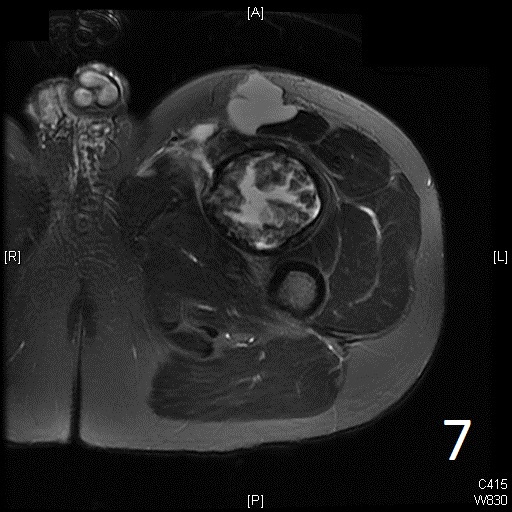

• 60% of fibrosarcomas are intramuscular (Fig. 2, 3, 5, 6, 7, 8)

• Well defined heterogenous mass on T2W (Fig. 4, 9)

Fig. 5-9: Axial and sagittal (Fig. 6) MRI shows a fibrosarcoma in the proximal quadriceps muscle that is isointense to muscle on T1W images, and a heterogeneous on T2W FS (Fig. 7, 8). The patient was treated with preoperative chemotherapy and the mass underwent extensive necrosis. The mass does not show any enhancement with contrast due to the extensive necrosis. There is only peripheral enhancement with contrast on T1W FS (Fig. 9).